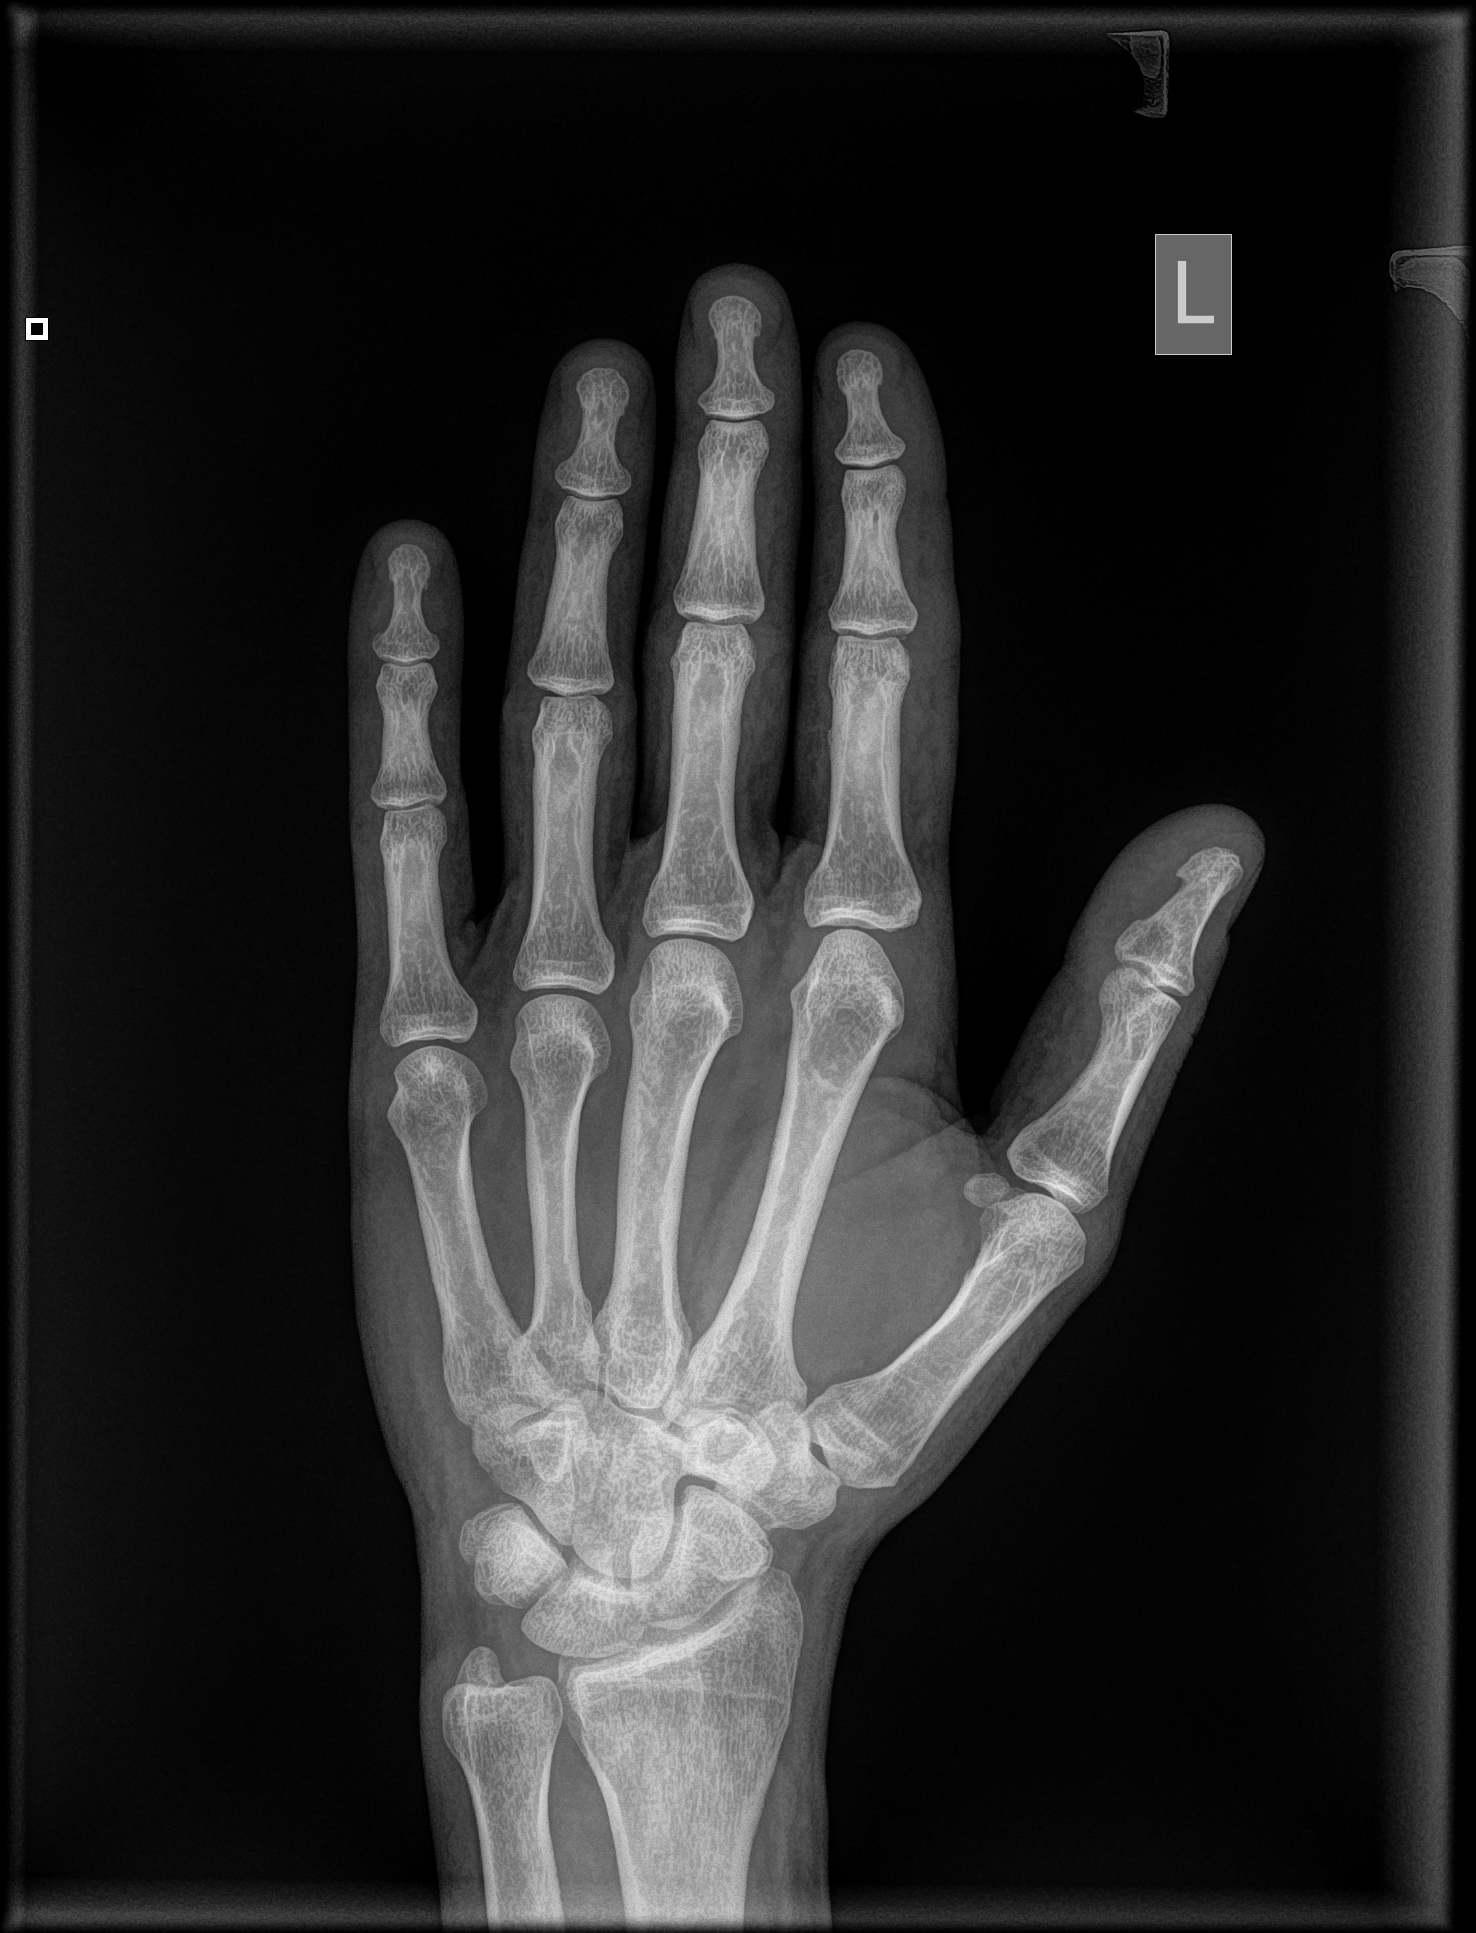

Uszkodziłem sobie palca wskazującego i jest nieco opuchnięty. Bardzo mocno wygiął mi się w górę, aż chrupnęło. Trochę boli mnie na wszystkich zgięciach. Wizytę u ortopedy mam za parę dni, a chciałbym się dowiedzieć, czy mam się czego obawiać. Załączam zdjęcia rtg wykonane dzisiaj.

IMG-0003-00001.jpg